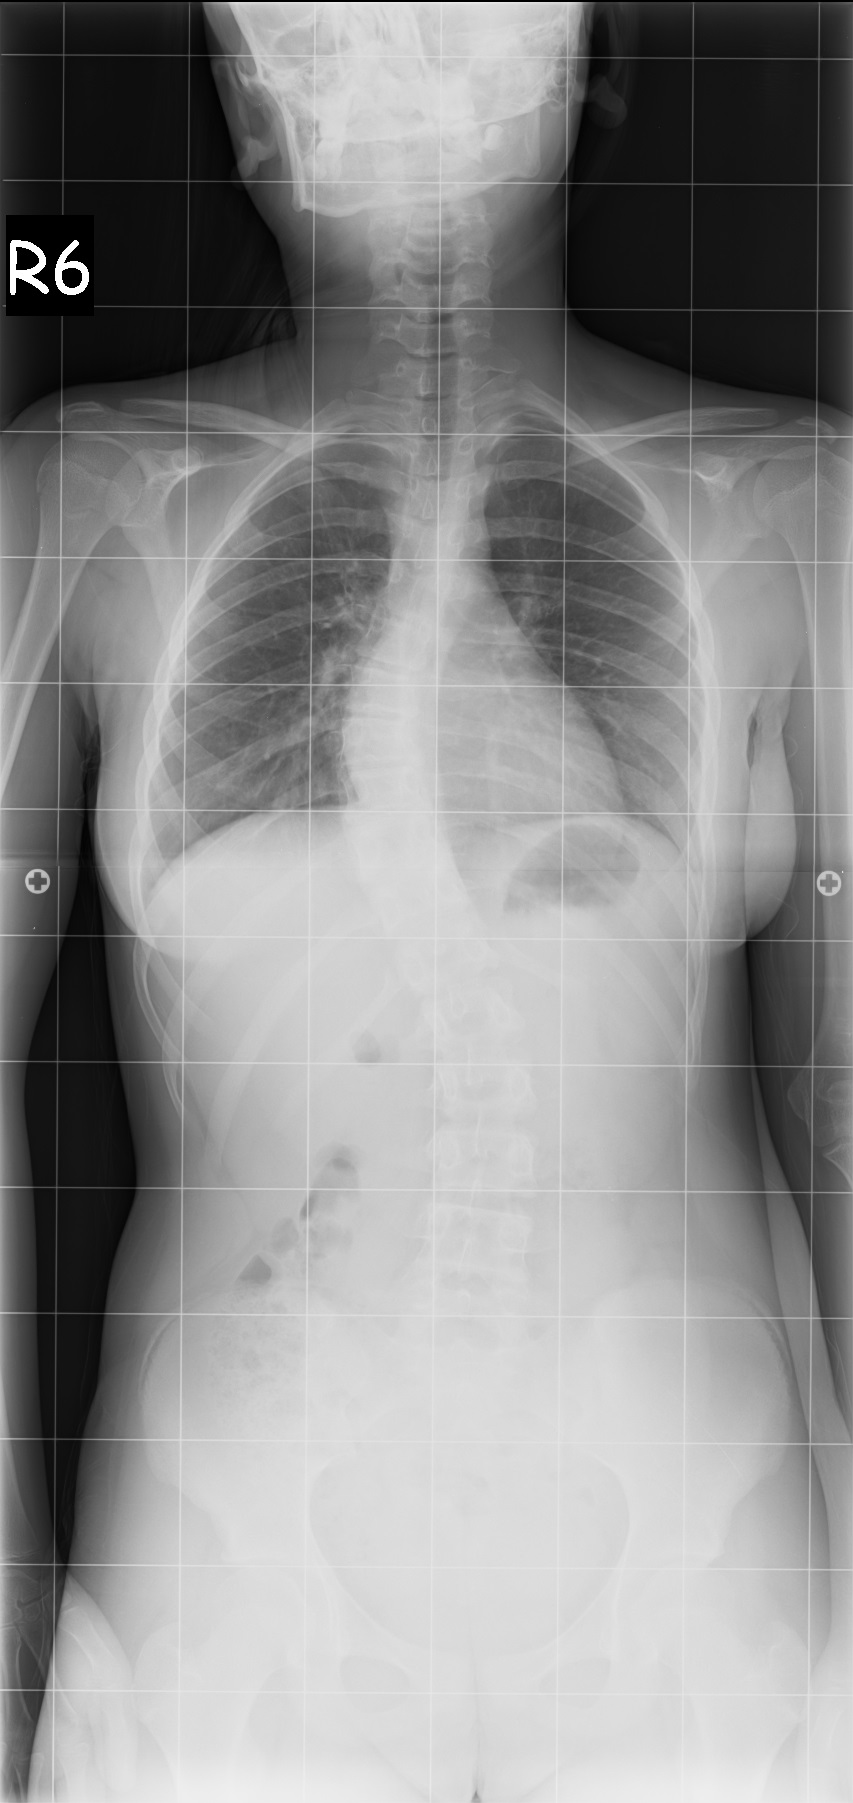

16 Yaşında Kadın Hasta

Ameliyat Öncesi